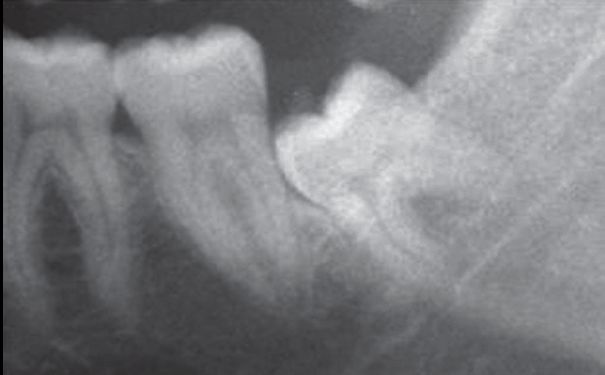

阻力存在的不同情况

A.邻牙阻力

B.远中冠部阻力

C.根肥大根部阻力大

D.邻牙阻力、冠部阻力和根部阻力同时存在